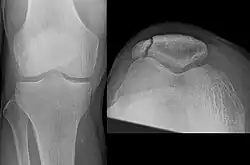

A fracture of the patella seen on a lateral view | |

Osteochondral fracture of patella